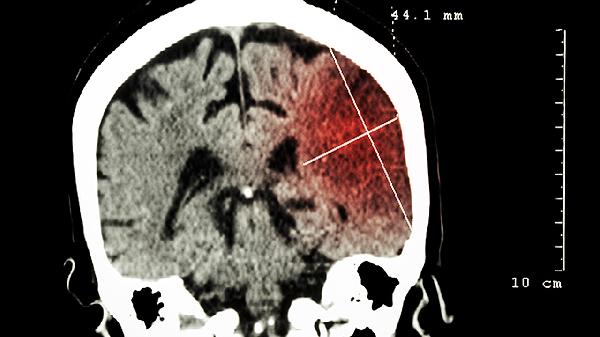

2、脑梗死

持续性脑供血不足可能导致局部脑组织坏死,形成脑梗死。患者会出现偏瘫、面瘫、吞咽困难等持续性神经功能缺损,头颅CT显示低密度病灶。发病机制涉及动脉闭塞、血流灌注不足,需紧急静脉溶栓或取栓治疗。恢复期可选用胞磷胆碱钠胶囊、丁苯酞软胶囊改善脑循环,配合银杏叶提取物片促进神经修复。